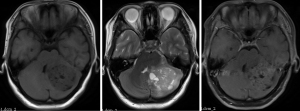

The inclusion criteria were as follows: (I) patients with available pathology (after resection); (II) patients with preoperative MRI data (see Figures 1,2); (III) patients with proven expression of the Ki-67 index by immunohistochemistry; Ki-67 index greater than or equal to 30% is defined as high expression, and Ki-67 index less than 30% is defined as low expression (see Figures 3,4); (IV) patients aged less than 18 years. A total of 271 patients were screened, and 181 patients were excluded due to the following reasons: (I) patients lacking Ki-67 expression by immunohistochemistry (n=96); (II) patients lacking at least one of the following MRI sequences: T1-weighted images (T1W), T2-weighted images (T2W), and contrast-enhanced T1-weighted images (CE-T1W) (n=71); and (III) patients with MR images that had motion or other kinds of artifacts that may affect subsequent segmentation and analysis (n=14). Finally, 90 subjects met the requirements and were included in this study (22 cases of Ki-67 index ≤30 and 68 cases of Ki-67 index >30). Clinical information (age and sex) and tumor characteristics (location, pathological type, and molecular type) are summarized in Table 1.